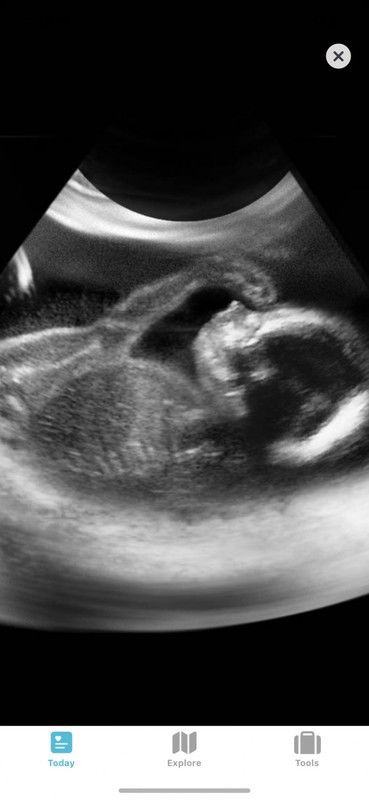

Assalamulaikum ibu2, sy sorg ibu yg ada 2 ank lelaki.. skg ne 6m prgnt,utk makluman ne last pregnancy sy sbb dua ank sy sblm ne emergency czer.. smlm scan doc ckp bby sy bby boy,sy brharap dpt bby girl mmndangkn ne last pregnancy 😔 Tp jelas Dan Terang sy nmpk bbird bby dlm scann smlm.. brharap sgt dpt mmiliki sorg ank prmpn tp nmpknya xde rezeki utk sy dpt bby girl.... tlg bg kta2 smngat utk sy😔 Edit: Thnks utk semua yg bg kata2 smngat.. alhamdulilah sy redha Dan bsyukur dgn tiap kurniaan Allah Cma sbgai mnusia biasa sy xlari dr mainan emosi,tp xde la nak mroyan atau bsedih bhari2 smpi mngabaikan atau kurangnya ksh syg dgn bby dlm prut ne sdikit pn xde rsa mcm tu.. Sy syg ank2 sy sumanya.. 🥰